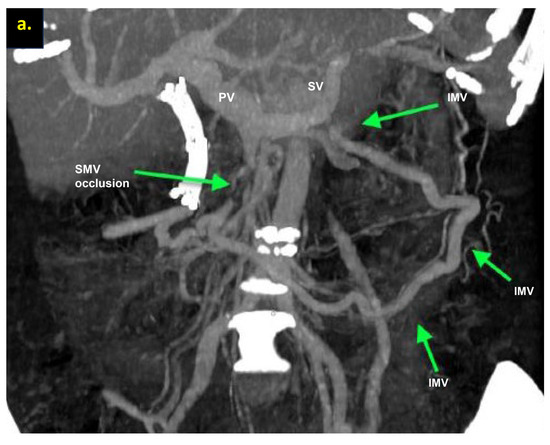

Total pancreatectomy with the SMV and all its tributaries resection with resection of IMV and its transposition into SV stump, combined with SMA resection and reconstruction for the uncinate PDAC in 71-year-old female. On CT the tumor invades the IMV and SMV (the last one is occluded), the SMV-SV confluence is preserved, and the IMV collaterals are well-developed with dilated intestinal veins, without right-sided vein collaterals and varices. (a) Three-dimensional MIP and (b) three-dimensional VR reconstructions show the dilated intestinal veins flowing into the IMV, which connects to the SV; (c) the picture of the operating field after the extended Whipple procedure with the SMV and all its tributaries resection without reconstruction. CHA—common hepatic, LGA—left gastric, SA—splenic, RHA—right hepatic, LHA—left hepatic, SMA—superior mesenteric arteries, CA—celiac artery, IVC—inferior vena cava.

Figure 7.

Pancreatoduodenectomy with the SMV and all its tributaries resection without reconstruction for the uncinate PDAC in 57-year-old female. On CT the tumor invades the SMV, which is occluded, the SMV-SV confluence is preserved, and the IMV collaterals are well-developed with dilated large collecting intestinal vein, without right-sided vein collaterals and varices. (a) Three-dimensional MIP and (b) three-dimensional VR reconstructions show the dilated large collecting intestinal vein flowing into the IMV, which connects to the SV; (c) the picture of the operating field after the extended Whipple procedure with the SMV and all its tributaries resection without reconstruction. CHA—common hepatic, LGA—left gastric, SA—splenic, SMA—superior mesenteric arteries, IVC—inferior vena cava; (d) the way of the intestinal blood flow after surgery.

In this study, only cases with full excision of SMV trunk and resection of all its tributaries, namely middle and right colic veins, ileocolic trunk, and all the first-order SMV branches (jejunal and ileal), without the reconstruction of above-mentioned vessels, were included. The usual length of the resected SMV with the branches in these cases was 7–8 cm (Figure 5 and Figure 7).

We used different post-processing CT techniques for the assessment of the peripancreatic vessels and collateral venous blood flow adequacy, such as shaded surface display, maximum intensity projection, and 3D volume-rendered (VR) reconstruction imaging. Now, when planning SMV resection with excision of all its tributaries for “low” pancreatic cancer, we consider CT-based 3D-VR reconstruction the best and most necessary option for the depiction of the collateral venous system. Compared to the other rendering CT techniques, VR is superior in delineating vessels, pancreatic parenchyma, the tumor, and adjacent structures (Figure 1a–d, Figure 5a,b, Figure 6a,b and Figure 7a,b,d) [43,44,45].